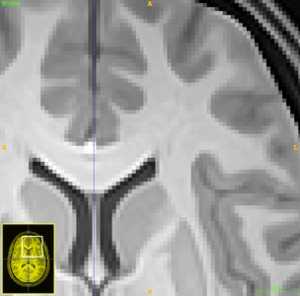

This document describes an ITK implementation of the adaptive patch-based image denoising algorithm described in cite{Manjon:2010aa}. This offering consists of the templated class itkPatchBasedDenoisingImageFilter interfaced through the DenoiseImage program which includes its own interface program. We include a couple of examples.